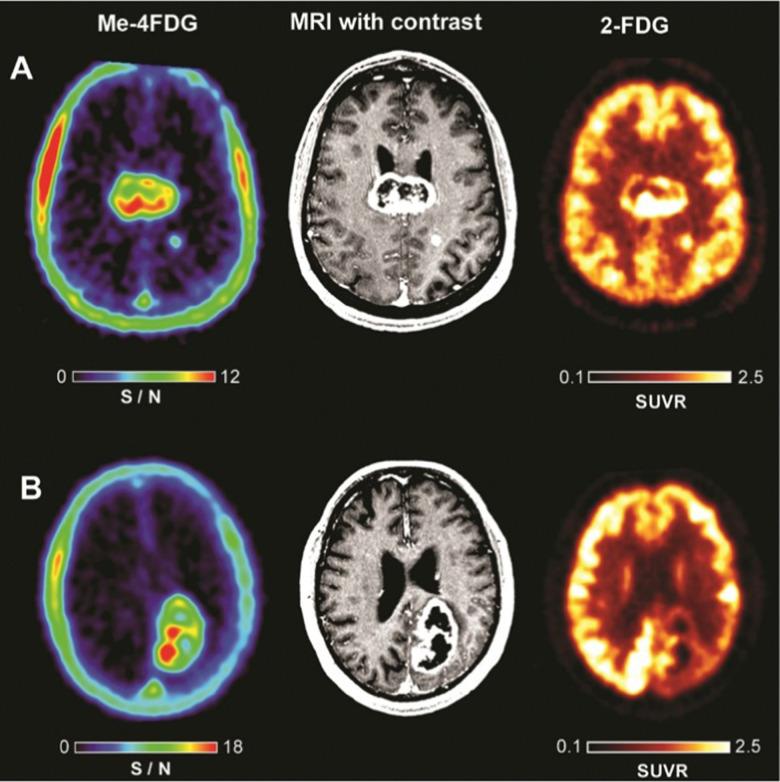

Carbohydrate diversity is foundational in the molecular literacy that regulates cellular function and communication. Consequently, delineating and leveraging this structure-function interplay continues to be a core research objective in the development of candidates for biomedical diagnostics. A totemic example is the ubiquity of 2-deoxy-2-[F]-fluoro-D-glucose (2-[F]-FDG) as a radiotracer for positron emission tomography (PET), in which metabolic trapping is harnessed. Building on this clinical success, more complex sugars with unique selectivities are gaining momentum in molecular recognition and personalised medicine: this reflects the opportunities that carbohydrate-specific targeting affords in a broader sense. In this Tutorial Review, key milestones in the development of 2-[F]-FDG and related glycan-based radiotracers for PET are described, with their diagnostic functions, to assist in navigating this rapidly expanding field of interdisciplinary research.

碳水化合物的多样性是调控细胞功能和通讯的分子基础。因此,阐明和利用这种结构-功能相互作用,一直是开发用于生物医学诊断的候选物的核心研究目标。一个典型的例子是 2-脱氧-2-[F]-氟-D-葡萄糖(2-[F]-FDG)作为正电子发射断层扫描(PET)的放射性示踪剂的普遍性,在 PET 中利用代谢捕获。在此临床成功的基础上,具有独特选择性的更复杂的糖在分子识别和个性化医疗方面正获得发展势头:这反映了在更广泛的意义上,碳水化合物特异性靶向所提供的机会。在本综述中,描述了用于 PET 的 2-[F]-FDG 及相关聚糖放射性示踪剂的发展中的关键里程碑及其诊断功能,以帮助人们在这个快速发展的跨学科研究领域中进行导航。